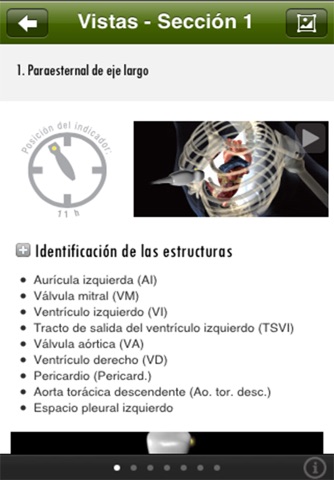

• Resume conceptos clave del examen de Ecocardiografía focalizado (FOCUS)

• Representa las vistas ecocardiográficas FOCUS con animaciones 3D

• Contiene un gran número de vídeos, animaciones de alta resolución, calculadora de rendimiento cardíaco, secciones de evaluación de función ventricular, líquido pericárdico, estado de líquidos, etc.